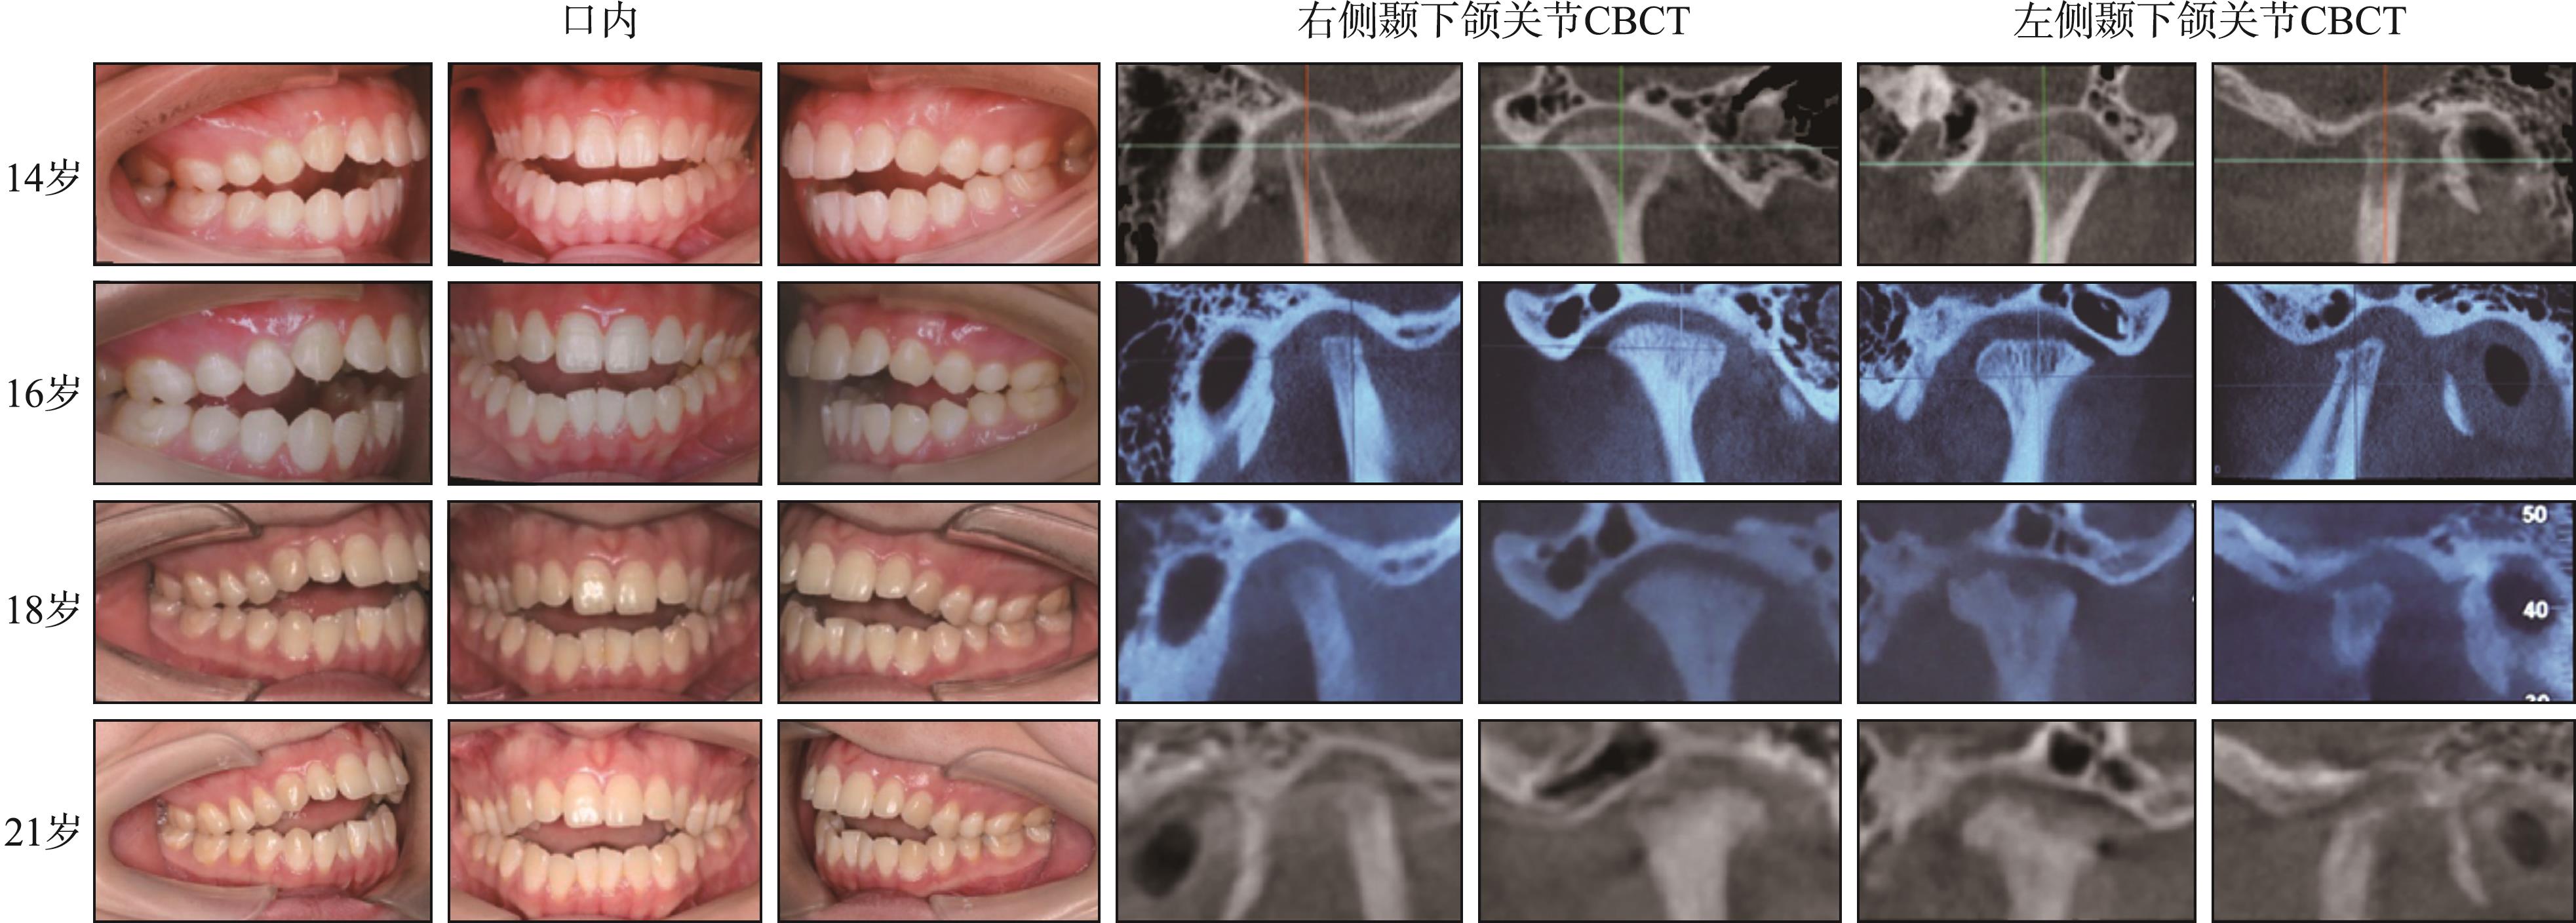

Fig 4

Changes of occlusion and condyle CBCT images in a patient with JICR"